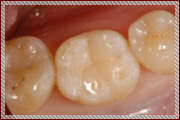

C1〜C2の治療:歯の表面と内側を削って詰める治療を行います

単に虫歯を削って詰めるといっても暗くて小さいお口の中で、

患者さまの健康な歯を傷つけずに虫歯の部分のみを取り除くことは、

非常に困難な作業です。

そのため従来の肉眼による治療では、

虫歯以外の健康な歯もたくさん削られて治療されていました。

その結果、治療後も歯がしみる、痛いなどの不快症状が残ることがあります。

当院では顕微鏡などの拡大鏡を使用することにより、

健康な歯を削らずに残し、

むし歯になってしまった部分だけを取り除いて

そこに接着材料をつかってきれいに封鎖する

MI治療(Minimum Intervention〜最小の侵襲)をおこなっております。

治療後の不快症状を最小限におさえ、なによりも従来の治療よりも歯を削らないため

患者さまの大切な歯を長持ちさせることができます。